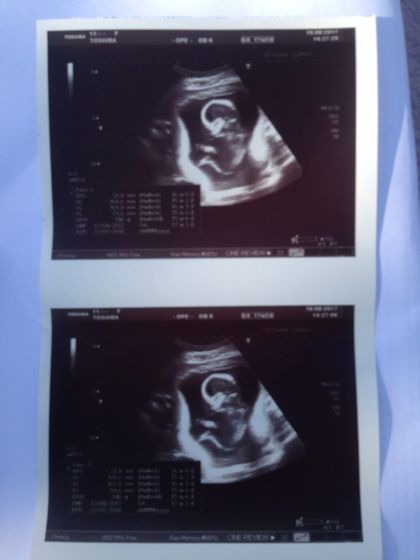

Все хорошо растём :) пол не сказали, но предположительно мальчик ))) видела как малыш бьется и крутится, жаль пока его шевелений не ощущаю…